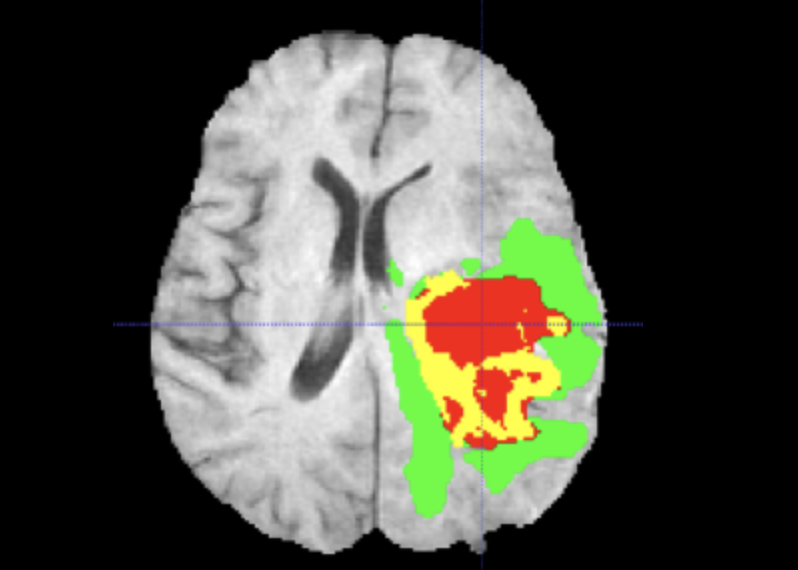

3D brain MRI scan showing tumor region

Brain MRI. Representative volumetric MRI scan used in the segmentation pipeline. The model processes 3D volumes, capturing spatial context across all three axes. Image credit: NVIDIA Research.